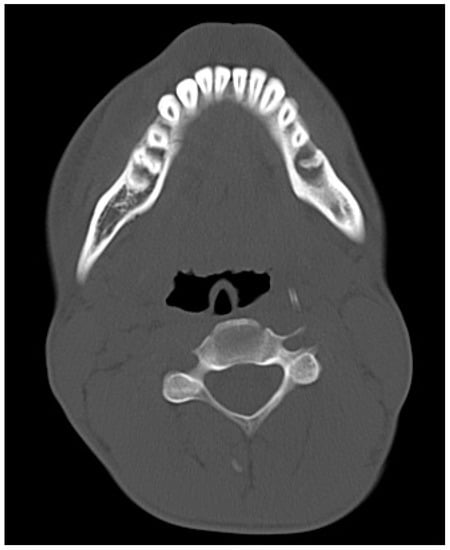

2. Materials and Methods